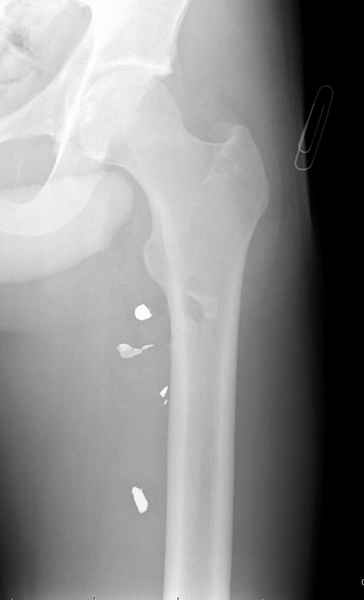

Больной с огнестрельным переломом бедра с вовлечением около 15% медиального кортекса, входное отверстие около 1 см в диаметре; стабильный, без сосудистых и неврологических признаков.

Входные маленькие отверстия от ранении просто игнорируются, никаких дренажей, как любое колотое ранения, они закрываются и были случаи через месяц. Конечно, ведется профилактика открытых ранении: сыворотки и т.д., но еще самое главное уделяем профилактике образования перелома из-за стресса в результате дефекта кортикального слоя.

Литературные данные о влиянии кортикального дефекта на стрессовые переломы в длинных трубчатых костях в основном встречаются в онкологии, например кортикальный дефект более 50% имеет больше шанса стрессовых переломов, чем в нашем случае.

Учитывая, что больной получил травму не во время визита в церковь, и он является одним из представителем 40 миллионного “outstanding itizen”, без медицинской страховки, без работы в свои 39 лет, и без надлежающей ортопедической дисциплины у которого отсутсвует страх стрессового перелома, было рекомендовано оперативное лечение: профилактическое антеградное интрамедуллярное штифтование.

Методика штифтования при отсутствии большой зоны перелома как при онкологических профилактических штифтованиях, расверливание интрамедуллярного канала проводим с предварительным наложением дополнительного дренажного отверстия в дистальном отделе бедра (в данном случаи в канале оставили 6.5 мм канюлированный шуруп), иначе при создании давления в канале во время сверления имеется опасность эмболизации легочной артерии тромбом.